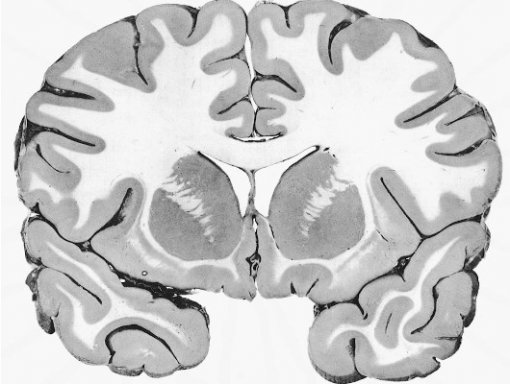

Beyin yarımkürelerinden enine kesit alındığında, dış kısımda boz madde, iç kısımda ise ak madde gözlenir.

Boz madde sinir hücrelerinin gövdelerinden, ak madde ise myelinli sinirlerin akson uzantılarından oluşmuştur.

Myelin, beyaz ve yağlı bir tabaka olduğundan böyle bir görünüm oluşur.